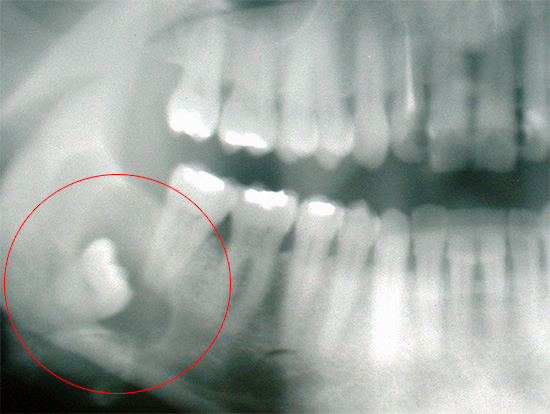

Qualsiasi dentizione difficile del dente del giudizio con dolore alla gengiva e ai tessuti circostanti richiede una diagnostica a raggi X. Per determinare la posizione del dente nella mascella (angolo di inclinazione, struttura, forma), viene utilizzato un ortopantomogramma (OPTG) o un'immagine panoramica di tutti i denti su entrambe le mascelle.

Puoi anche effettuare uno scatto mirato su un visiografo, un dispositivo che trasmette un'immagine al monitor di un computer. Dopo che il dentista sa con cosa ha a che fare, pianifica un'operazione: spiega i rischi per il paziente, il tempo approssimativo della procedura, le caratteristiche del periodo postoperatorio dopo la rimozione del dente del giudizio, ecc.

Spesso i denti inferiori della saggezza iniziano a tagliare e ferire, ma non hanno fretta di apparire sulla superficie delle gengive.Nelle immagini è possibile osservare come il dente "saggio" sia quasi in inclinazione orizzontale rispetto a quello adiacente, per cui in alcuni casi clinici inizia anche a provocare dolore. Anche nel dente del giudizio che non è ancora apparso sulla superficie delle gengive, possono verificarsi carie e sue complicazioni, poiché i batteri cariogeni passano facilmente sotto la gomma dietro il penultimo "sette".